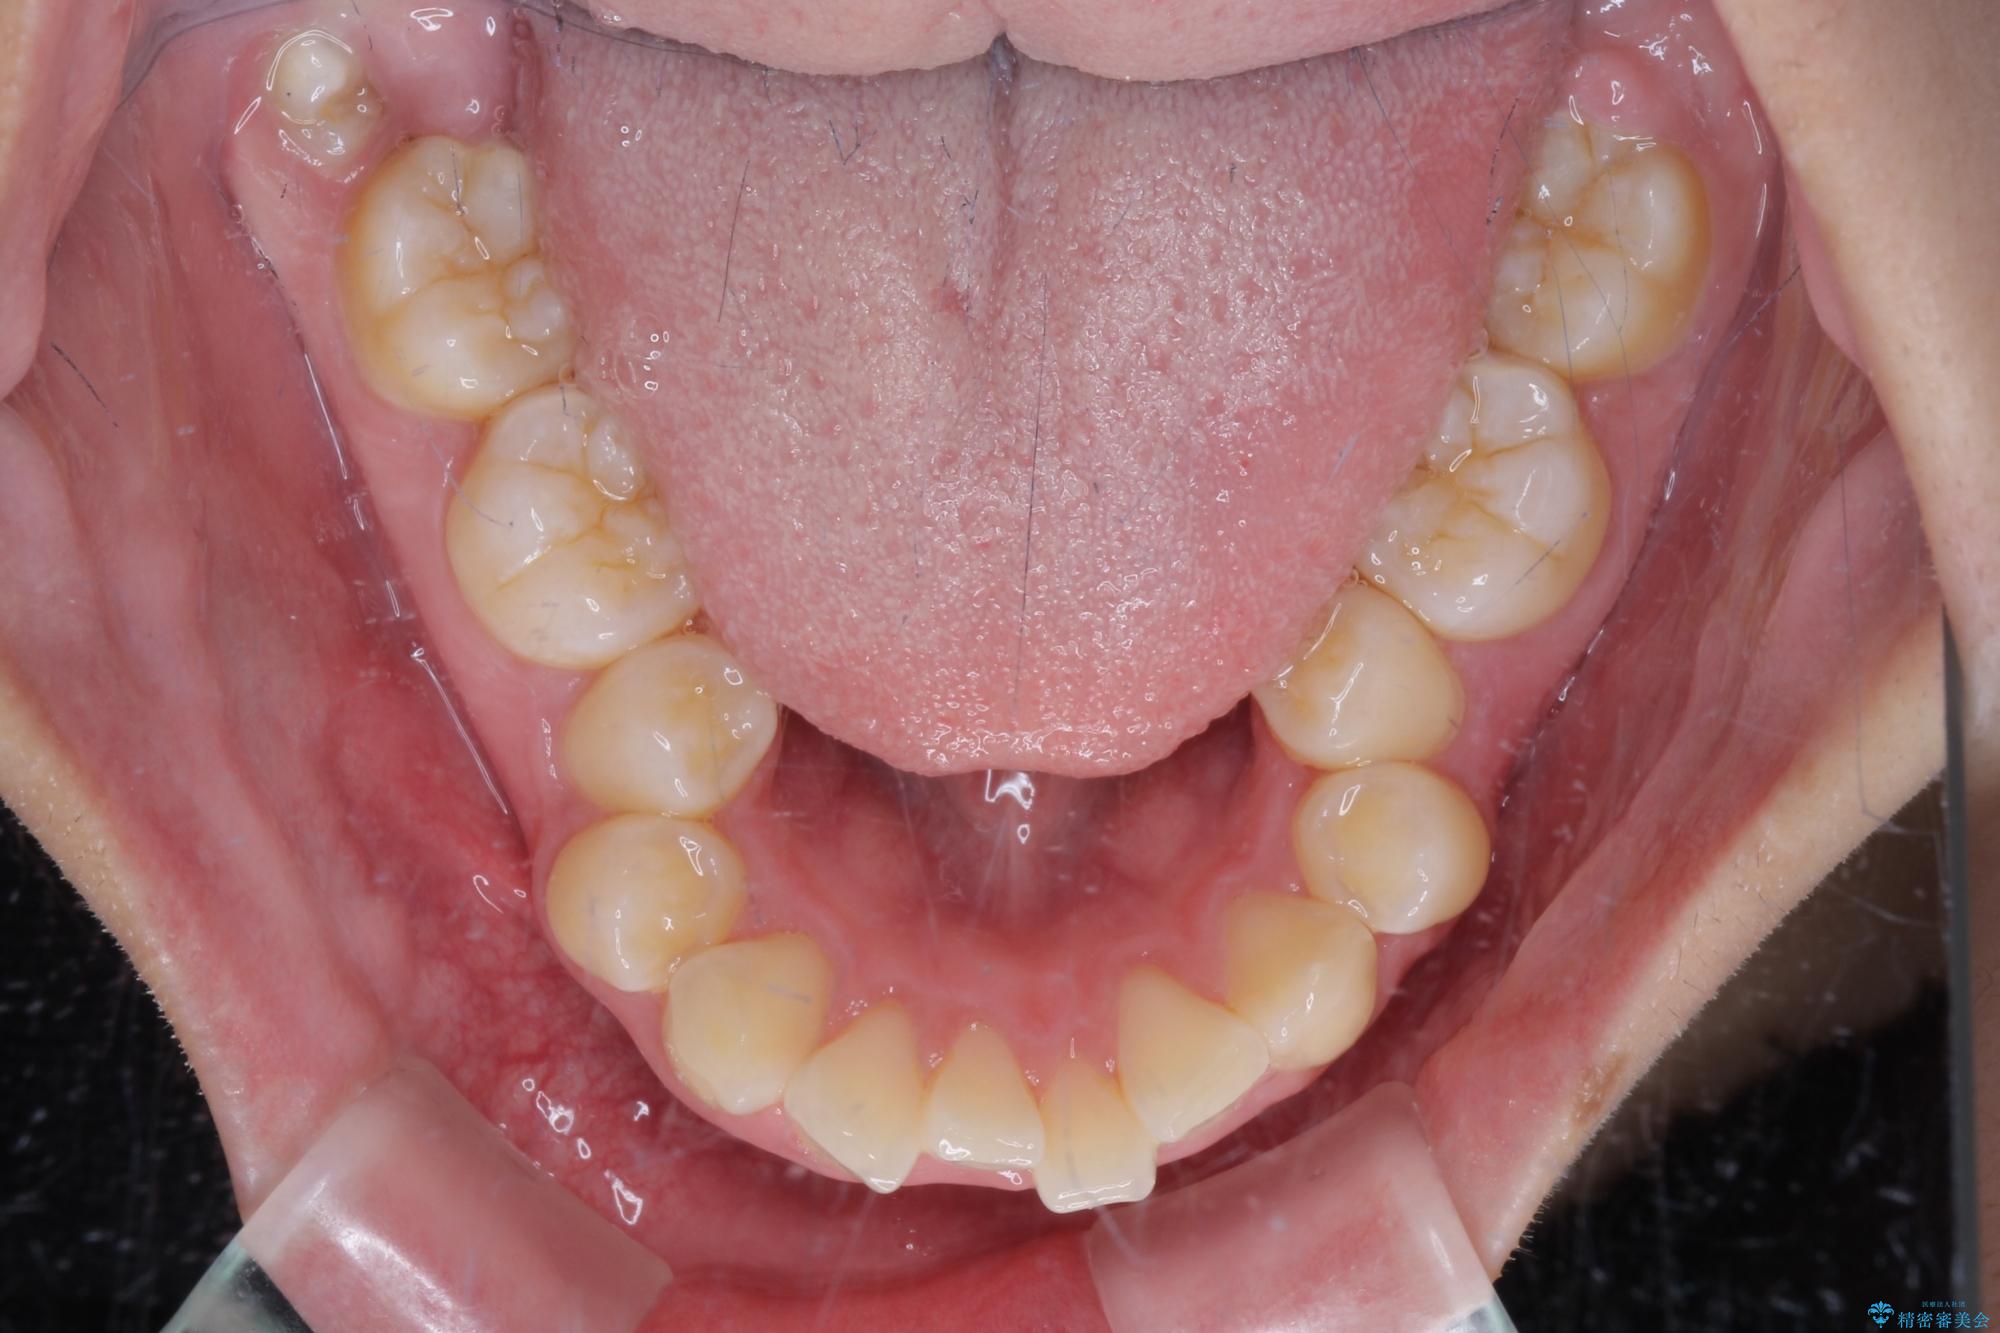

- 上顎前歯が飛び出していて唇がうまく閉じられないとのことで来院された患者様です。

くちばしのように前歯が突出していたため、口元を積極的に引っ込めるために、上下左右の小臼歯4本を抜歯することとしました。

また、上顎歯列が下顎に対して前方位に位置していたため、補助装置を用いて上顎歯列を後方に移動させ、より積極的に口元を下げるようにしました。

上下正中位置を改善するため、左下はイレギュラーに第二小臼歯を抜歯しました。そのため治療期間の長期化が予想されましたが、2年半ほどで期待通りの歯列に仕上げることができました。